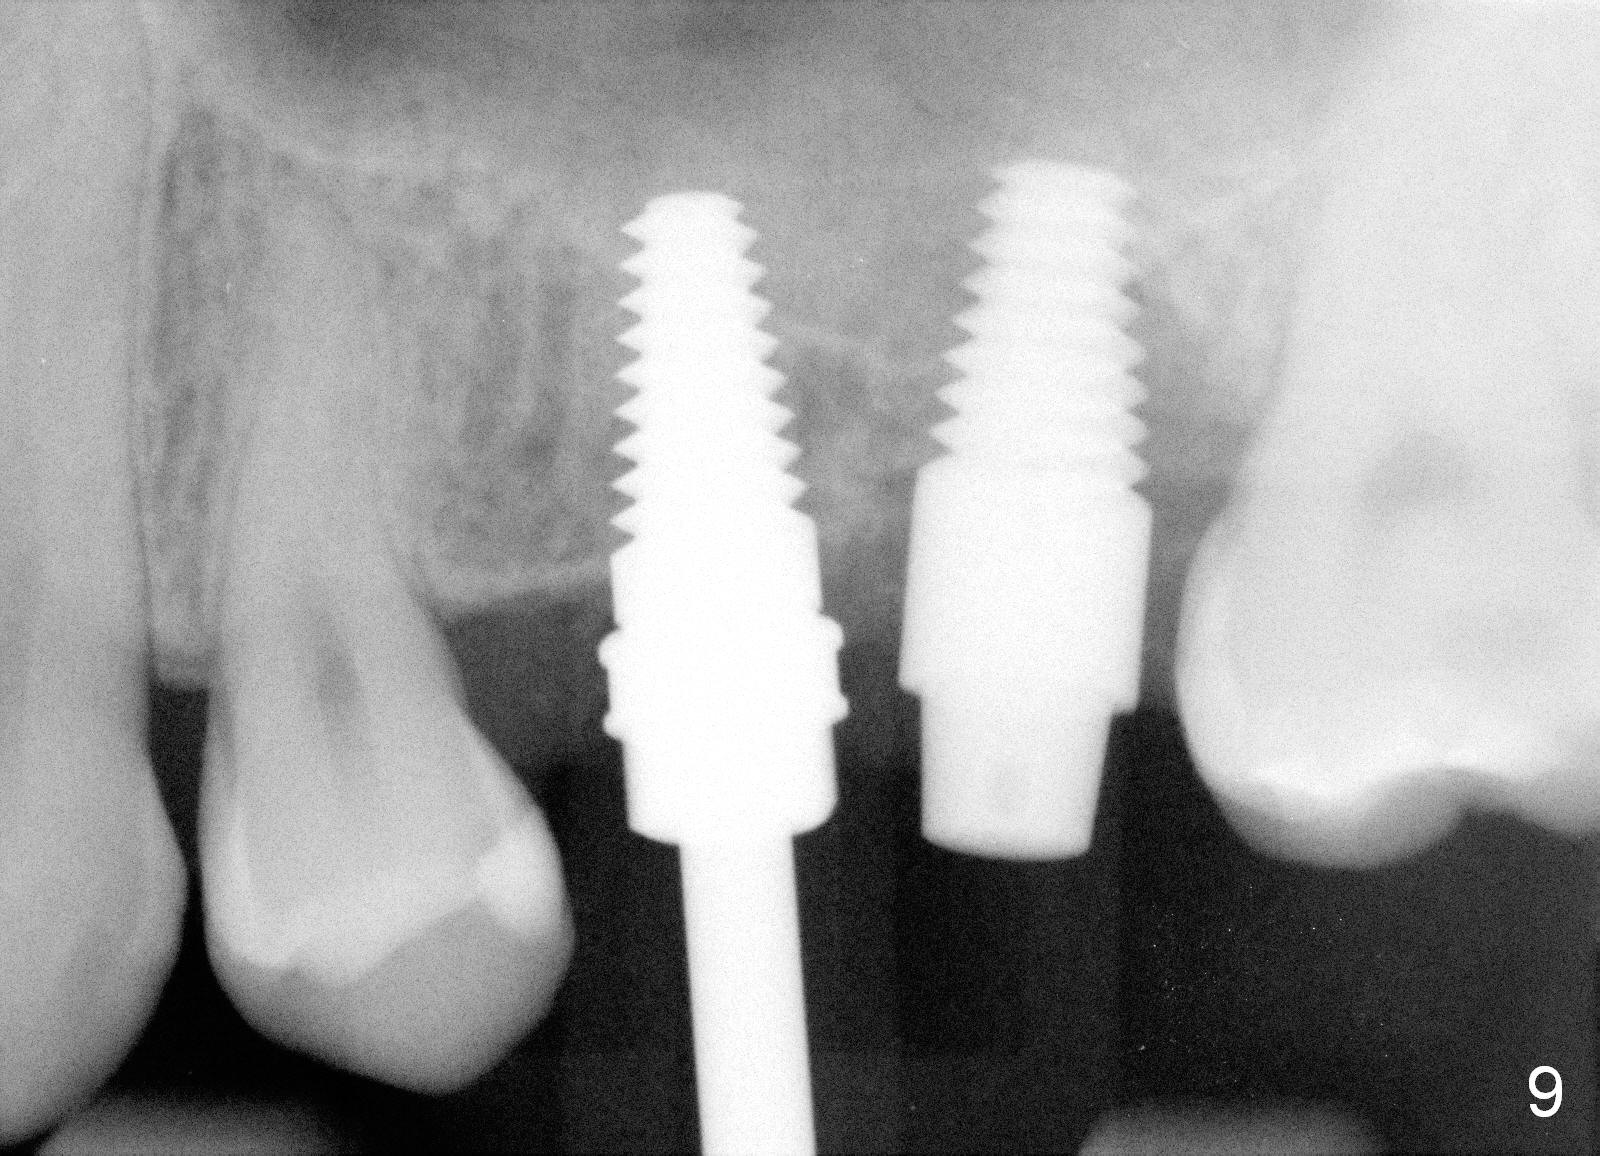

The patient returns for #13,14 implant placement. The ridge appears to be wide buccolingually (Fig.1 mirror view). A 4 mm tissue punch is used for access at the sites of #13 and 14. Osteotomy is initiated by using 3 mm trephine bur at the depth of 4 mm at both sites; 2 mm pilot drill is used to continue osteotomy at 8 mm deep at the site of #13. Sinus lift is accomplished by using tapered osteotomes 2,3 mm 6 mm deep, followed by 4.5x11 mm tap (Fig.2 T); 2 mm pilot drill (P) is reinserted into #13 osteotomy site with inadvertently penetrating the sinus floor. When the tap is removed from the site of #14, the sinus membrane is also found to be perforated. The sinus membrane at both sites is repaired by insertion of collagen dressing before bone graft. A 4x11 mm one-piece implant is placed at the site of #13 slowly hoping that it does not re-perforate the sinus membrane (Fig.3 O). Due to limited restorative height, the abutment portion of the one-piece is expected to be trimmed (Fig.4 O). In case of implant complication or failure, the implant may be difficult to be removed. Therefore the implant at the site of #14 is two piece one (Fig.4,5 I/A, 5x11 and 4x3 mm, respectively). The insertion torques for #13 and 14 are 35/40 and >60 Ncm. Immediate provisionals are canceled mainly because of patient's inability to open wide for long. Perio dressing is placed instead after adjustment of the height of the abutments. The patient experiences one episode of light nasal hemorrhage a few hours postop. Although the patient takes Amoxicillin for 1 week periop, the implant at the site of #13 dislodges 1 months postop (Fig.5). Immediate re-placement with a larger 2 piece one is canceled because of mild infection mesiobuccal to the implant at the site of #14 (Fig.6 >). Exploration around the latter implant reveals possible thread exposure in a small area. After copious irrigation with normal saline, Arestin is placed. Two months post exfoliation, the site is re-entered (Fig.7,8). There is a lingual defect. Osteotomy is initiated as buccal as possible. A 4.5x11 mm tapered tap penetrates the sinus floor without tearing the membrane (Fig.9). The same-sized implant is placed (25/30 Ncm) with sinus lift (Fig.10 *). The lingual defect is bone grafted. There is dehiscence lingually 7 days postop (Fig.11). Impression for final restoration is taken 1.5 months postop because of pending wedding. The crown has been in function for 2.5 months.